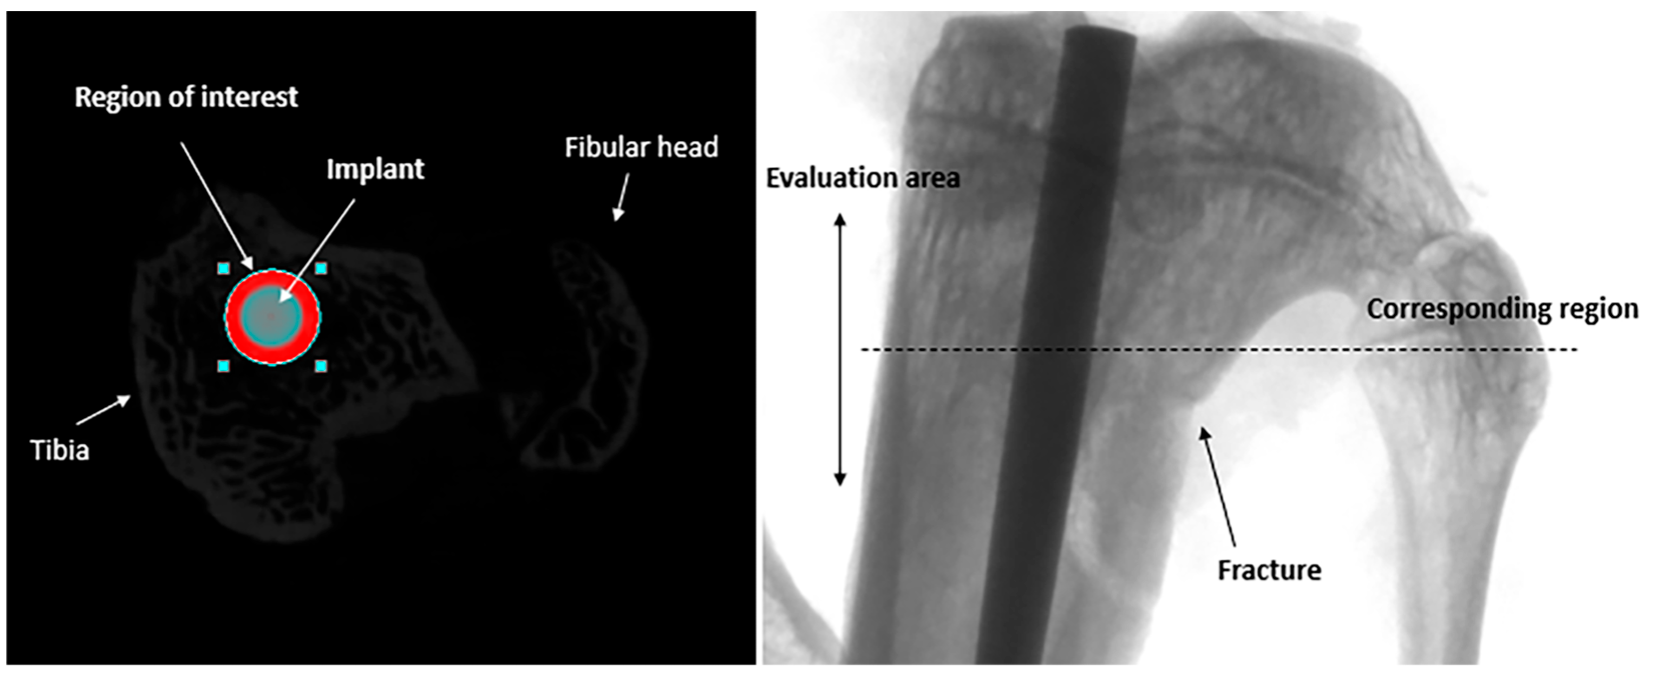

The newly formed bone around the implant was evaluated through micro-CT scans. The results were obtained by defining, in bone, a circular region of interest with a 0.5 mm width around the implant (1 mm), as shown in Figure 4. The region of interest (ROI) was centered on the implant with a round shape in the metaphysis of the tibiae, and data were collected from the evaluation of a length of bone of 3 mm. The top selection image was chosen at the exact separation of the fibular head from the tibia, including the fracture site. The same investigator performed the evaluation in the blind group. The groups were compared using the percent bone volume (PBV) BV/TV (%) parameter. In the groups where a rat died and was removed from the research, another tibia was chosen at random for micro-CT analysis.

Figure 4. A transversal image (CTAnalyzer 1.13.0.0, Bruker, Belgium) of a tibial implant and the region of interest (ROI) with the corresponding frontal micro-Ct image.